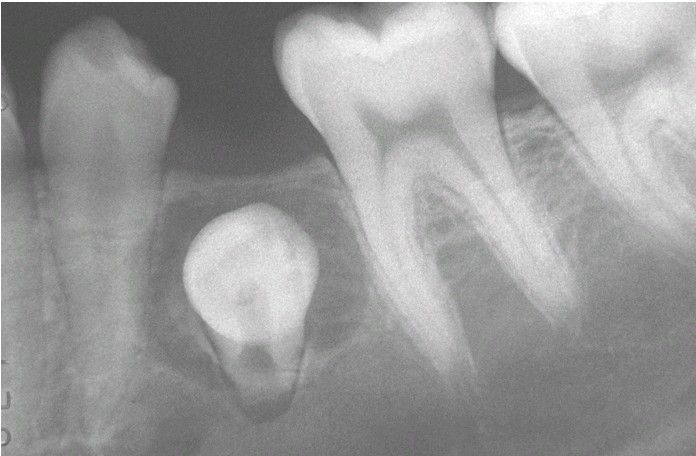

Dentigerous Cyst or Enlarged Follicle

. Radiolucent lesion involving the crown of an unerupted mandibular premolar. Distinction between a dentigerous cyst and an enlarged follicle for a lesion of this size by radiographic and even histopathologic means is difficult, if not impossible.